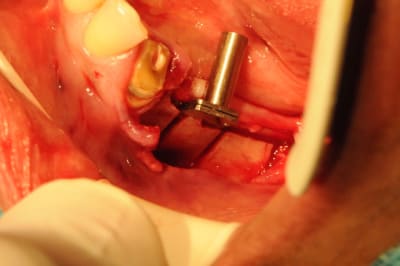

4:

évolution

Tatum D1

quand je fais du deux temps (expansion, comblement avec du biomat et intervention c'est parce que l'os est à sa limite et ne peut gérer une reconstruction et une ostéo-intégration.

Il s'agit alors d'os D1 ou de crête d'environ 1mm.

exemple: